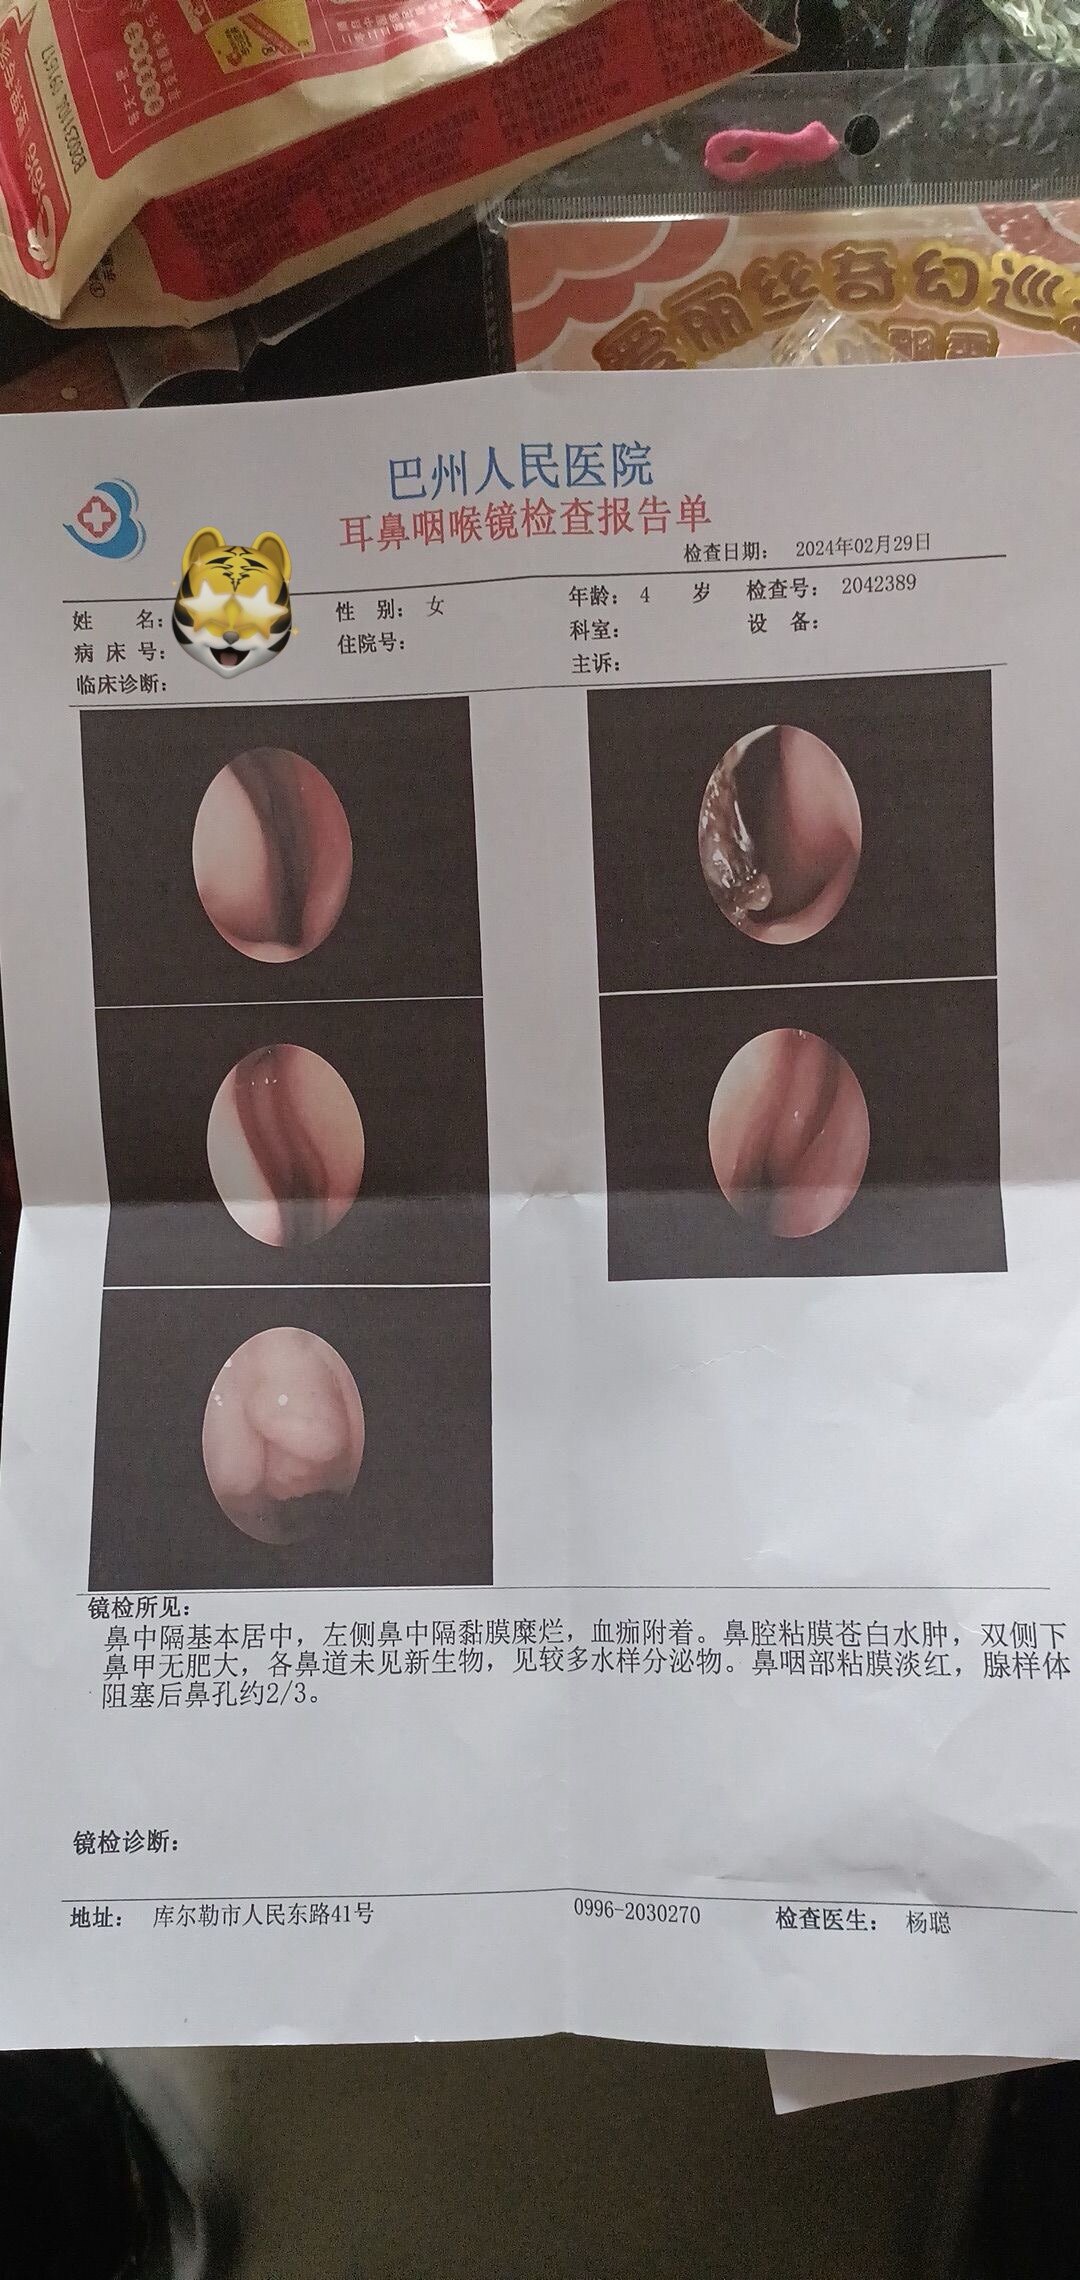

之前同一天做过“鼾症兄弟”、“鼾症兄妹”和“鼾症父女”,这是第一次给“鼾症母女”同一天手术。这对母女来自新疆巴音郭楞,重度鼾症父亲37岁,因为扁桃体肥大,自小打鼾,4年前产后打鼾加重,伴夜间憋醒,严重影响睡眠,当地医生建议患者戴呼吸机,但是她无法耐受呼吸机。电话咨询后,下定决心来广州找我手术。同时她也把4岁女儿打鼾和张口呼吸的情况也详细告诉我,鼾症女儿因为扁桃体3度肥大,腺样体堵塞后鼻孔2/3,造成张口呼吸,对于这样的孩子,一定需要早点手术干预,不然会影响面部发育和生长发育,甚至智力发育。所以我就让她们母女一起来广州找我手术。手术时发现母女俩的扁桃体肥大,因为女孩子4岁,我常规保留双下极扁桃体的1/5和腺样体的1/5。希望母女手术后身体早日恢复正常!有一个安稳的睡眠质量,健健康康的生活!

腺样体肥大